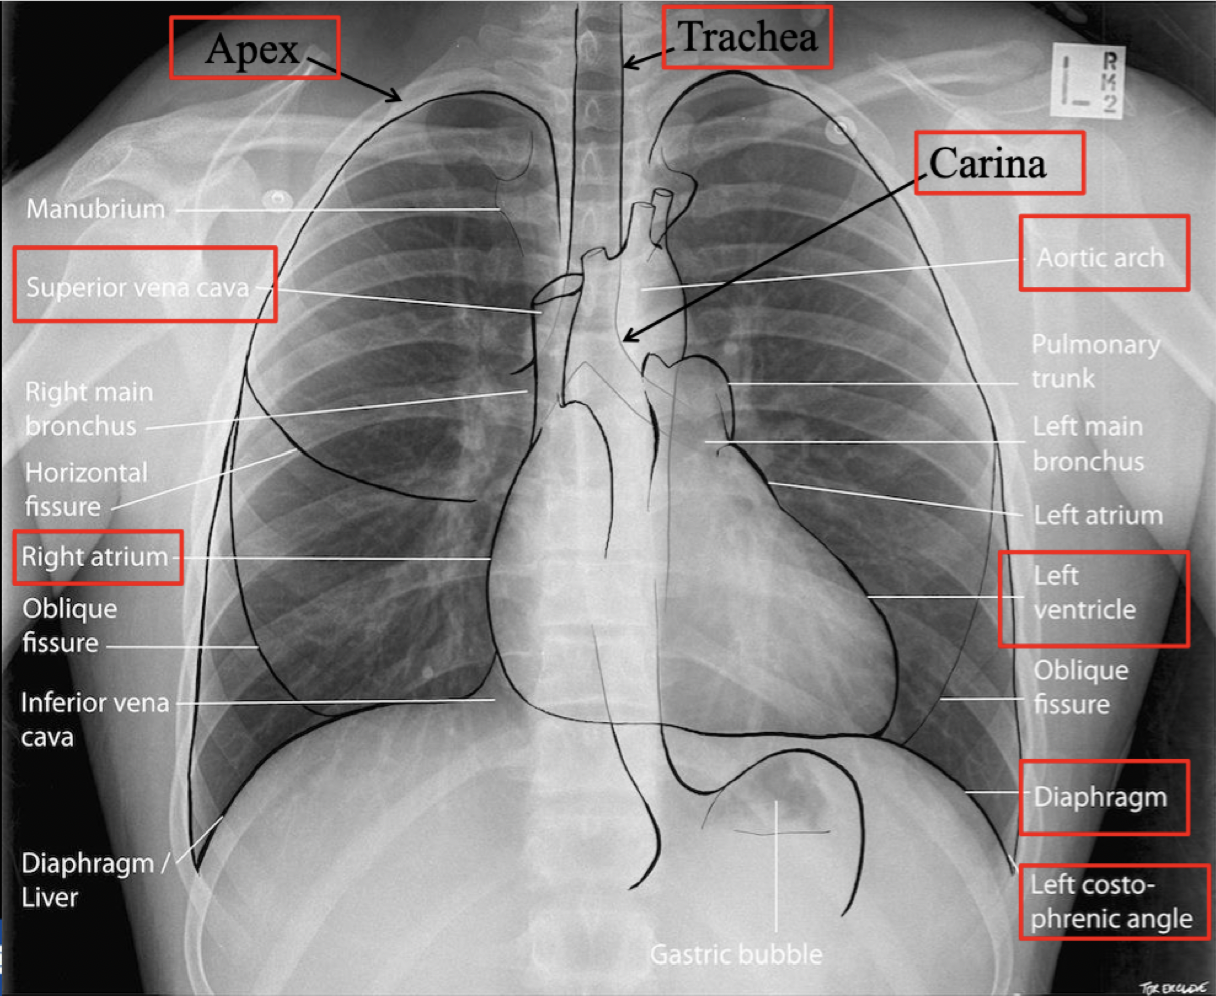

Plasser anatomiske strukturer

How well did you know this?